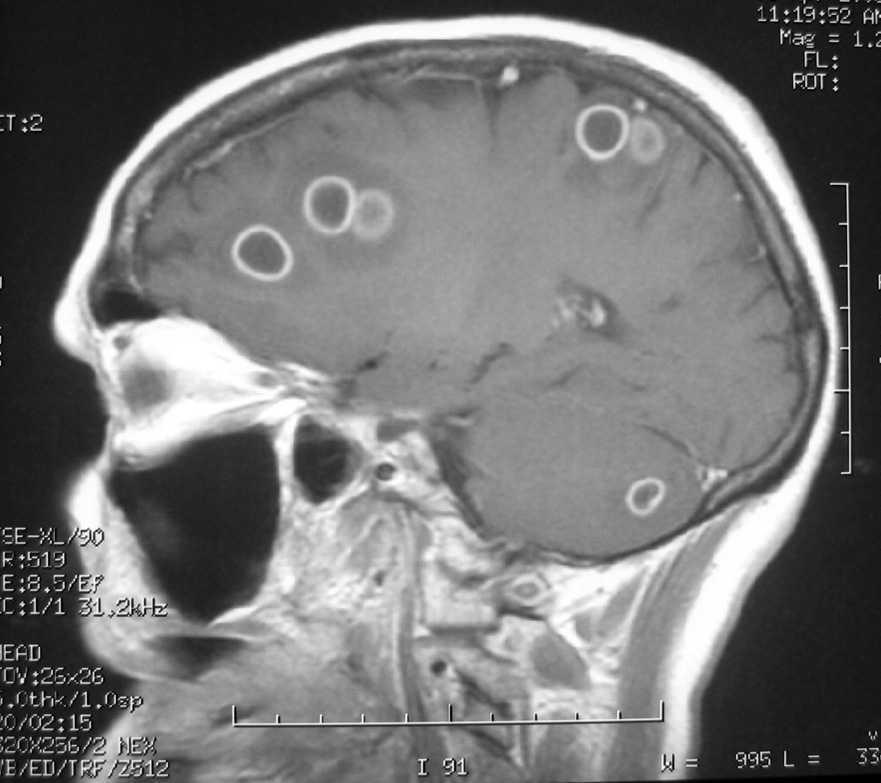

Figura 2.

Mujer de 60 años con uveítis crónica en tratamiento con corticoides. Ingresa por cuadro de tres días con cefalea, vómitos y fiebre, disminución del nivel de conciencia y disfasia. Al ingreso presentaba una temperatura de 39 ºC, crisis tónico clónicas y flúter auricular con hipotensión. Se intubó y conectó a ventilación mecánica. Se le realizó tomografía computarizada craneal con contraste y resonancia magnética donde se ven múltiples lesiones en ambos hemisferios cerebrales y en el cerebelo con captación en anillo (figs. 1 y 2) y edema asociado, que brillan en difusión, compatibles con abscesos piógenos. No se aisló ningún germen en sangre, orina, aspirado traqueal ni líquido cefalorraquídeo. Se realizaron estudios para encontrar el foco de la infección, exploraciones del área otorrinolaringológica, fondo de ojo, ecocardiografía transesofágica, etc., siendo todos normales. Tras tratamiento con meropenem la paciente evolucionó favorablemente, siendo dada de alta asintomática al Servicio de Neurología.